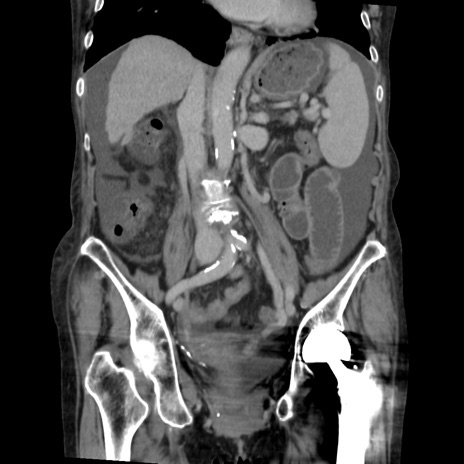

症例31(冠状断像)

【症例】80歳代 女性

【主訴】腹部膨満感

【現病歴】他院にて肝硬変にてフォロー中。1週間前から便秘、腹部膨満感、臍部腫瘤あり受診となる。

【既往歴】肝硬変

【身体所見】腹部膨隆あり、皮膚変化なし、疼痛なし。

【データ】WBC 4600、CRP 0.25